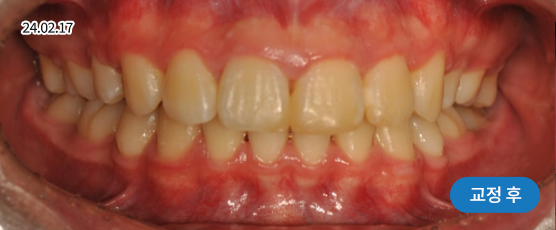

덧니교정 Solution

덧니는 악궁 크기, 얼굴형, 골격 등을 고려해 발치, 비발치를 현명하게 판단하여 치료합니다.

치아가 정렬될 공간을 확보하기 위해, 경우에 따라 소구치(작은 어금니)를 발치할 수 있습니다.

* 본 사진은 동일 조건에서 촬영되었으며, 환자 본인의 동의를 얻어 게재되었습니다.